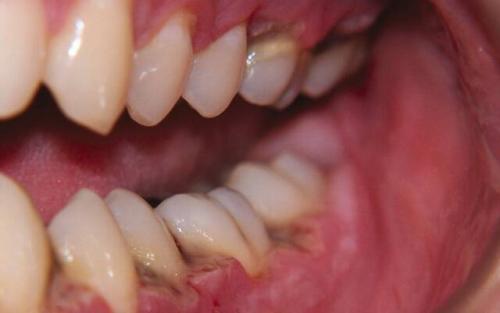

Кариес и темные десны

С кариесом знаком каждый житель планеты Земля. Это вялотекущее разрушение твердых тканей зуба, которое вызывают неблагоприятные внешние и внутренние факторы.

Кариес деминерализует эмаль, постепенно в дентине образуется отверстие. Если не вылечить болезнь своевременно, патологический процесс достигнет пульпы и периодонта. Это опасное состояние , которое грозит потерей зуба. Кариес также может протекать скрыто. Разрушение происходит в глубине зуба, внешне изменения заметить трудно.

Запущенный кариес отражается на состоянии десны. У основания зуба она чернеет, может появиться небольшая припухлость.

Некроз зуба и его корня в десне — черное пятно

Травма челюстей и десен

Черное пятно на десне может оказаться гематомой, следствием сильного физического действия:

- удар по лицу, по челюсти;

- выбитый зуб;

- чрезмерное давление на десну ортопедических конструкций, слишком твердой пищи;

- удаление зуба с осложнением.

Физическая травма приводит к разрыву мелких сосудов , кровь вытекает в тканевое пространство. На десне образуется лиловый или черный синяк, иногда шишка. Постепенно высвобожденный гемоглобин разлагается, пятно меняет цвет на коричневый и желтоватый. О травме человеку должно быть известно, чтобы избежать нежелательных последствий , нужно обратиться за консультацией к специалисту.

Киста десны после пломбирования — темное пятно

Последствием серьезной травмы десны может быть инфекция, воспаление и даже некроз тканей. Поэтому запускать проблему нельзя.